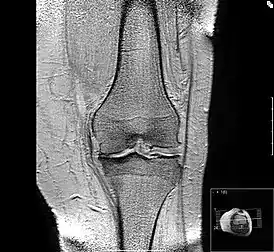

Вторая стадия неизбежно переходит в третью — стадия тяжёлого артроза. Её признаки — выраженная костная деформация опорной площадки сустава, которая изменяет ось конечности. Несостоятельность, укорочение связок сустава приводит к патологической подвижности сустава или в сочетании с жёсткостью суставной сумки — к резкому ограничению естественных движений — контрактур. Хроническое воспаление и хронический болевой синдром обычно сопровождают 2 и 3 стадию.

Исход артроза — полное разрушение сустава с формированием анкилоза — полной неподвижности сустава или неоартроза с неестественной подвижностью. Это сопровождается тяжёлым нарушением функции конечности. В последнее время, не дожидаясь исхода заболевания, все чаще применяют специальные операции по замене сустава протезом — эндопротезирование сустава. На рисунке изображена типичная для терминальной стадии артроза коленного сустава варусная деформация колена в сочетании с боковой патологической нестабильностью коленного сустава. Артроз блоковидного или шаровидного сустава, такого как тазобедренный, завершается анкилозированием. При этом замыкание сустава обычно происходит в нефизиологическом (порочном) положении конечности. В данном случае мы видим бедро в положении сгибания и приведения, при котором нога укорачивается, а ось конечности и биомеханика опорно-двигательной системы существенно нарушается.